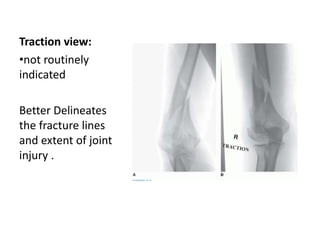

Traction view:

•not routinely

indicated

Better Delineates

the fracture lines

and extent of joint

injury .